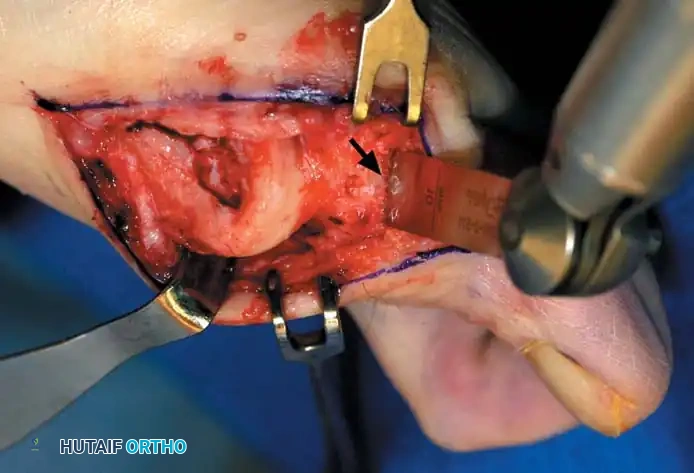

• By sharp dissection, raise the periosteum and the capsule dorsally and plantarward from the base of the proximal phalanx to the proximal edge of the medial eminence (Fig. 78-15). At the proximal end of the medial eminence, avoid releasing the proximal bony attachments of the medial capsule on the metatarsal neck (especially in the dorsal direction) in an attempt to expose the medial eminence. To ensure adequate exposure without disruption of this proximal attachment, a longitudinal capsular incision is suggested.

• Elevate the capsule by sharp dissection dorsalward and plantarward to expose the dorsal aspect of the metatarsal head, the entire medial eminence, and the plantar plate. A periosteal elevator is not recommended because of the possibility that the proximal attachments of the capsule may be released.

Fig. 78-15 Modifi ed McBride procedure. Capsule is opened, and attachment of capsule on metatarsal neck (arrow) is carefully preserved.

• After inspecting the metatarsophalangeal joint for degenerative changes, loose bodies, or synovial abnormalities, remove the medial eminence by fi rst scoring with an osteotome its proximal edge where the eminence meets the shaft. Always consult the preoperative radiographs to determine how much of the medial eminence should be removed.

• Using the same osteotome or a power saw, begin the exostectomy distally at the parasagittal groove, and direct it medially toward the scored area on the metatarsal shaft (Fig. 7817). If a power saw is used, a 9-mm blade, rather than a 4to 5mm blade, is preferred. The medial direction of the osteotomy prevents splitting of the metatarsal shaft, especially if the proximal edge of the osteotomy has been scored as recommended.

• After the medial eminence has been removed, use a small rongeur to round off the dorsal and plantar edges of the medial aspect of the metatarsal head. Rasping the raw bone concludes the initial stage of the procedure. Use bone wax on the raw surfaces of bone of the metatarsal head.

ADDUCTOR TENDON AND LATERAL CAPSULAR RELEASE

• Begin the second stage with a dorsal longitudinal incision beginning 2 to 3 mm proximal to the dorsal aspect of the fi rst web space to avoid web contracture postoperatively; extend it proximally between the fi rst and second metatarsal heads for 3 to 4 cm (Fig. 78-18). This allows adequate exposure of the adductor insertion into the base of the proximal phalanx, the lateral head of the fl exor hallucis brevis muscle converging on the fi bular sesamoid, and the entire lateral capsule from the extensor hallucis longus muscle to the plantar plate.

• The main portion of the adductor tendon inserts into the base of the proximal phalanx just plantar to the longitudinal axis of the phalanx. It also has a smaller insertion, along with the lateral head of the fl exor hallucis brevis muscle, into the fi bular sesamoid. The simplest technique to identify the insertion of the adductor hallucis tendon is to place a small, pointed, curved hemostat on the dorsolateral base of the proximal phalanx, slide it fi rmly plantarward, and lift the hemostat dorsally and laterally; the tip of the instrument usually rests in the axilla of the insertion of the adductor tendon (Fig. 78-19A). This is comparable to securing the iliopsoas tendon for tenotomy at the lesser trochanter.

• When the primary insertion is released, grasp the tendon with forceps or a hemostat, and, with traction, displace it dorsally and laterally toward the second metatarsal so that further dissection is on the medial side of the adductor or push the sesamoid sling laterally through the previously placed medial incision to aid exposure.

• While spreading the fi rst and second metatarsal heads with a small Inge retractor, heavy-duty two-tooth retractors, or a Weitlaner retractor, hold the adductor tendon under tension, which facilitates exposure. The lateral head of the fl exor hallucis brevis muscle, the lateral border of the fi bular sesamoid, and the slip of the adductor tendon (confl uent with the lateral head of the fl exor hallucis brevis muscle) come into view in the depths of the wound.

• All attachments of the adductor into its conjoined insertion with the lateral head of the fl exor hallucis brevis muscle into the fi bular sesamoid must be severed; with traction on the adductor, it freely and independently moves without tethering the fi bular sesamoid (Fig. 78-19B).

• This deep transverse intermetatarsal ligament, which lies just plantar to the adductor, may be released by the incision along the lateral border of the sesamoid. If not, release this ligament, carefully preserving the neurovascular bundle immediately beneath it, and incise the lateral capsule. Mann emphasized that release of the deep transverse metatarsal ligament endangers the neurovascular bundle to the fi rst web space, which lies immediately beneath this ligament. Sliding a small Freer elevator between this ligament and the neurovascular bundle would protect the latter structures.